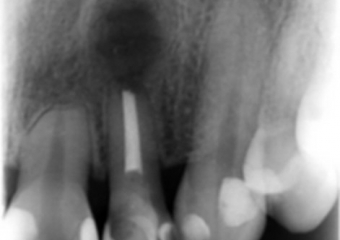

Raio x inicial com presença de lesão periapical no incisivo lateral superior esquerdo - Clínica Cliniface

Raio x inicial com presença de lesão periapical no incisivo lateral superior esquerdo